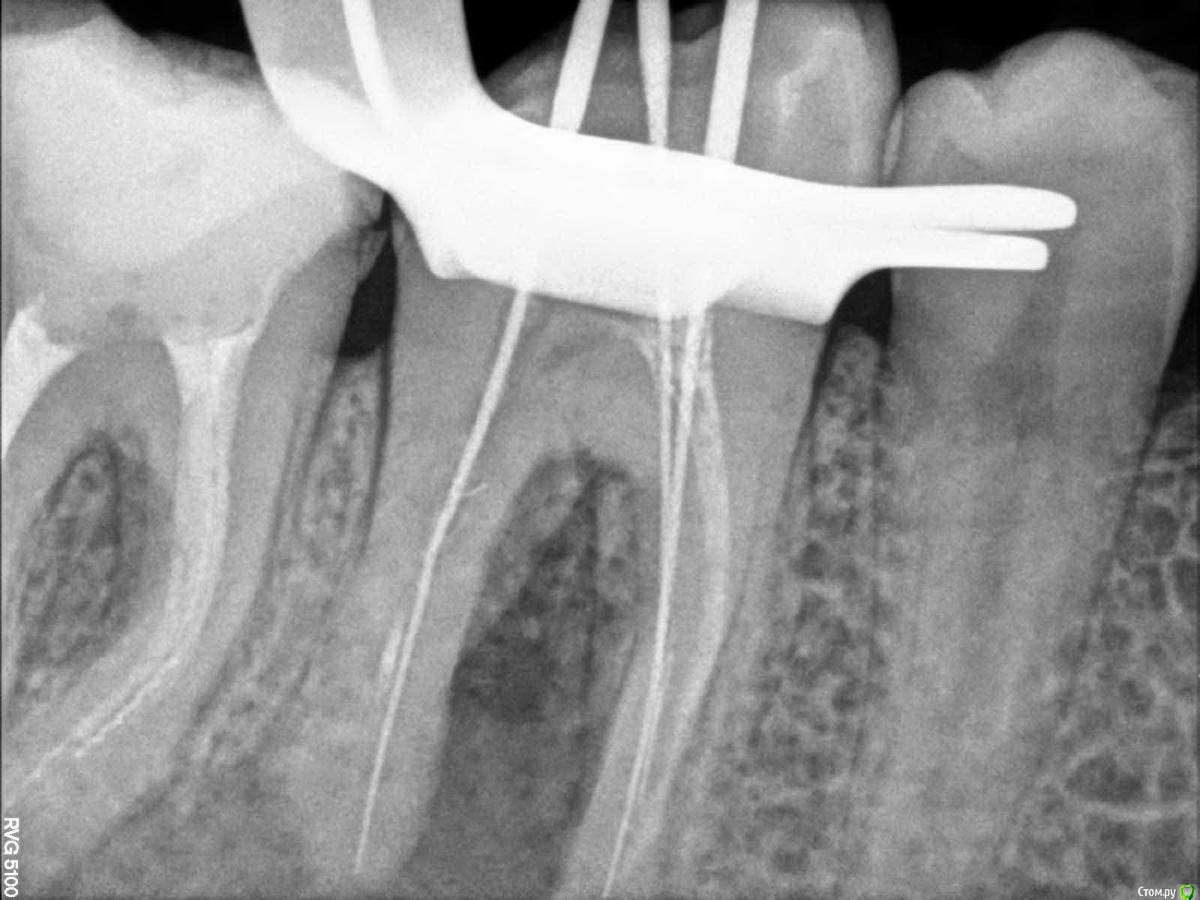

Bibika2020 Опубликовано 31 мая, 2020 Поделиться Опубликовано 31 мая, 2020 Всем добрый день. Предыстория:В 2018 году на зубе 46 откололся кусочек сзади и зуб начал сильно болеть. Зуб до этого был уже депульпирован лет 5-10 назад (уже не помню) и стоял со световой пломбой. В 2018 г. провели восстановление коронковой части зуба пломбой, в каналы не лазили.В 2019 году в районе этого зуба появился свищ, но зуб никак не беспокоил. Текущая ситуация:Весной 2020 года зуб начал реагировать на холодное и горячее и надкусывание средней степенью боли.Первое посещение врачаОбратился к врачу в марте (снимок 1 и 2). Доктор сказал, что можно попробовать перелечить каналы и сохранить зуб. Из трёх каналов один был не запломбирован, в двух других была гуттаперча. Доктор провела механическую и медикаментозную обработку двух каналов: незапломбированного и одного с гуттаперчей и заложила кальцийсодержащую пасту, поставила временную пломбу, выписала антибиотик 5 дней.Облегчение почувствовалось сразу. Через неделю свищ прошёл. Ещё через неделю опять появился. Второе посещение врачаКак раз подходило время очередного приёма, но доктор уже был другой в том же месте.Снимки 3 и 4. Доктор провела механическую и медикаментозную обработку двух каналов и заложила кальцийсодержащую пасту. Сказала, что временная пломба была сильно не герметична поэтому микробы попадали в зуб. Положила фум ленту и сделала световую пломбу 10 апреля. Свищ опять на какое-то время пропал и снова появился через пару недель. Третье посещение врачаНа следующем приёме доктор сделал снимок с гуттаперчей вставленной внутрь свища, на снимке гуттаперча дошла до низа левого канала, как раз того, который изначально не было запломбирован N лет назад (снимка, к сожалению, нет). Дальше подключился хирург и сказал, что такой зуб нужно удалять, т.к. гранулирующий периодонтит (если я правильно запомнил). Сейчас прошло почти 2 месяца есть неприятные ощущения от зуба и свищ то появляется, то пропадает. ВопросЗуб жалко удалять, на мой взгляд, он нормальный.Хотелось бы услышать мнение врачей, есть шанс сохранить зуб и что делать? Ссылка на комментарий

Bibika2020 Опубликовано 1 июня, 2020 Автор Поделиться Опубликовано 1 июня, 2020 (изменено) Вот ещё на снимке смущает (обвёл красным):1. на правых корнях 7го зуба волнистые линии это не остатки инструмента?2. непонятная загагулина на проблемном канале 6го зуба. что это может быть ? А что означает раскрытие полости зуба? Это его рассверливание, чтобы легче было к каналу доступ осуществить? Изменено 1 июня, 2020 пользователем Bibika2020 Ссылка на комментарий

dok1 Опубликовано 1 июня, 2020 Поделиться Опубликовано 1 июня, 2020 Щестёрка с булавоообразным утолщением корня. Пошла резорбция апекса. Плюс резорбция в просвете каналов. Я в шестой неверю . По этому бы рекомендовал удалить. Седьмой, если удастся извлечь инструмент, можно вылечить Ссылка на комментарий